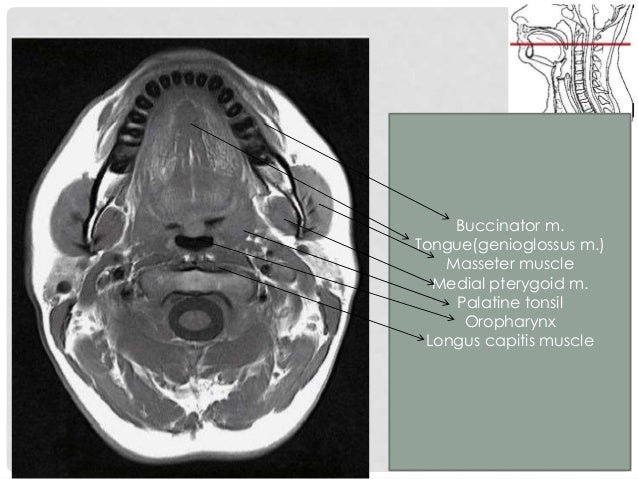

Oral Cavity, Pharynx

pharynx genioglossus hyoglossus oropharynx

Axial Head & Neck

anatomy axial neck head

CT Series | Radiology Key

ct axial series neck radiology key